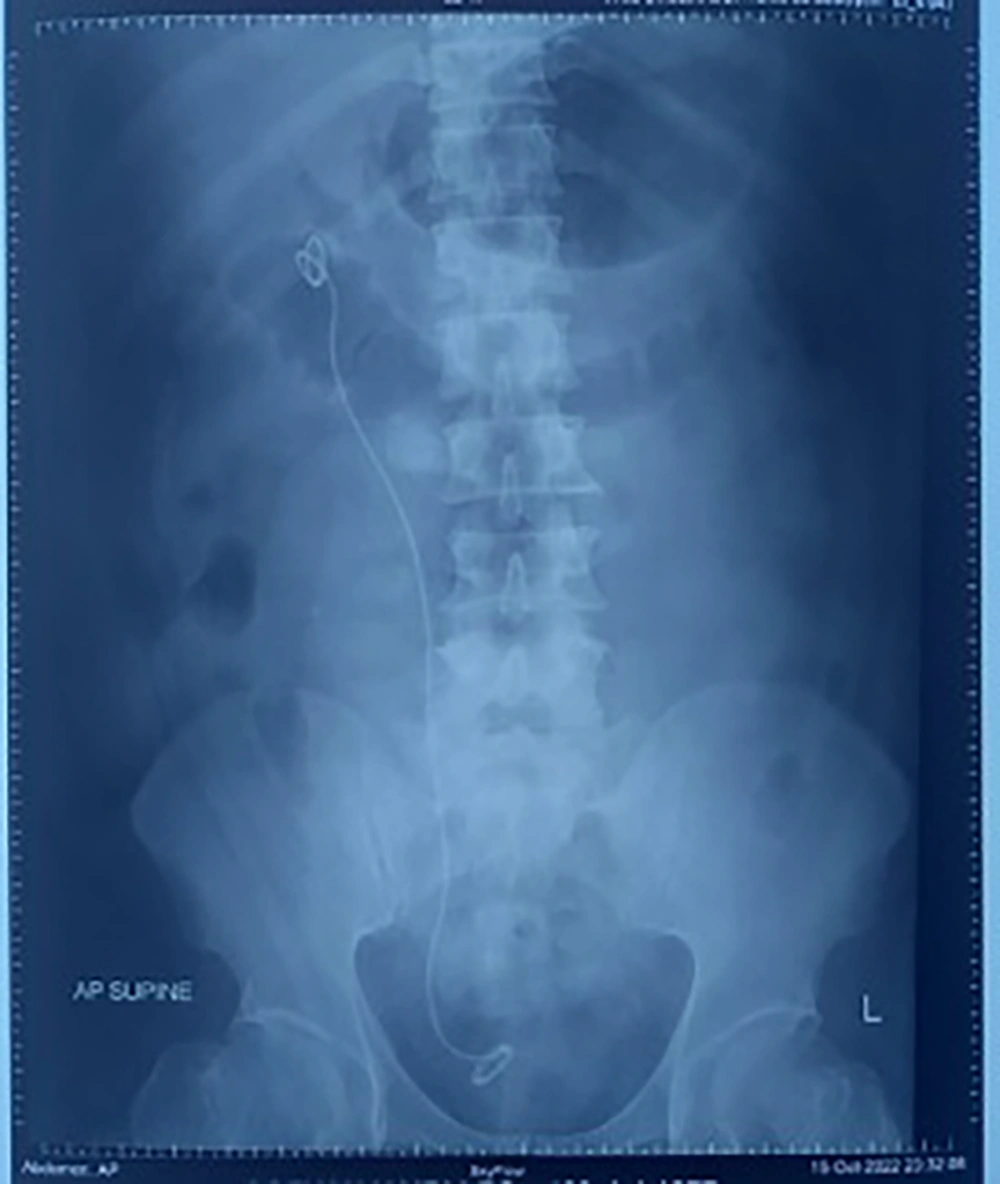

No residual stones were visualized on the post-operative KUB X-ray (Figure 4). The post-operative complete blood count was normal, with hemoglobin recorded at 16.5 g/dL. The patient was discharged from the hospital 2 days after surgery.